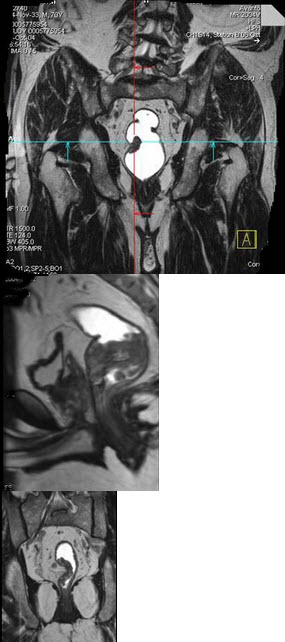

男,70岁,下腹部腹胀、腹痛、排便困难,逐渐加重,MRI示直肠内不规则充盈缺损,请选择最佳诊断结果( )